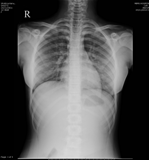

A 13 year old girl with a DOUBT that she had swallowed a single end pointed needle 30 minutes prior to attending the fast track op.

No h/o any foreign body sensation neck, no abdomen pain

With these X RAY ,

doubt is cleared , there is no forign body

BUT…..